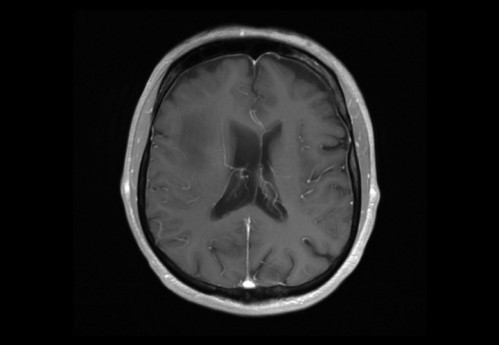

Sie behandeln einen 48-jähriger Mann, von Beruf Architekt. In der Anamnese erfahren Sie, dass er leidenschaftlich Gitarre spiele und er berichtet, dass ihm seit zwei Wochen in der rechten Hand die nötige Koordination fehle. Auch das Plektrum würde ihm immer wieder aus den Fingern gleitet.

Eine Magnet-Resonanz-Tomografie (MRT) des Kopfes wurde durch den ambulant behandelnden Neurologen bereits veranlasst.